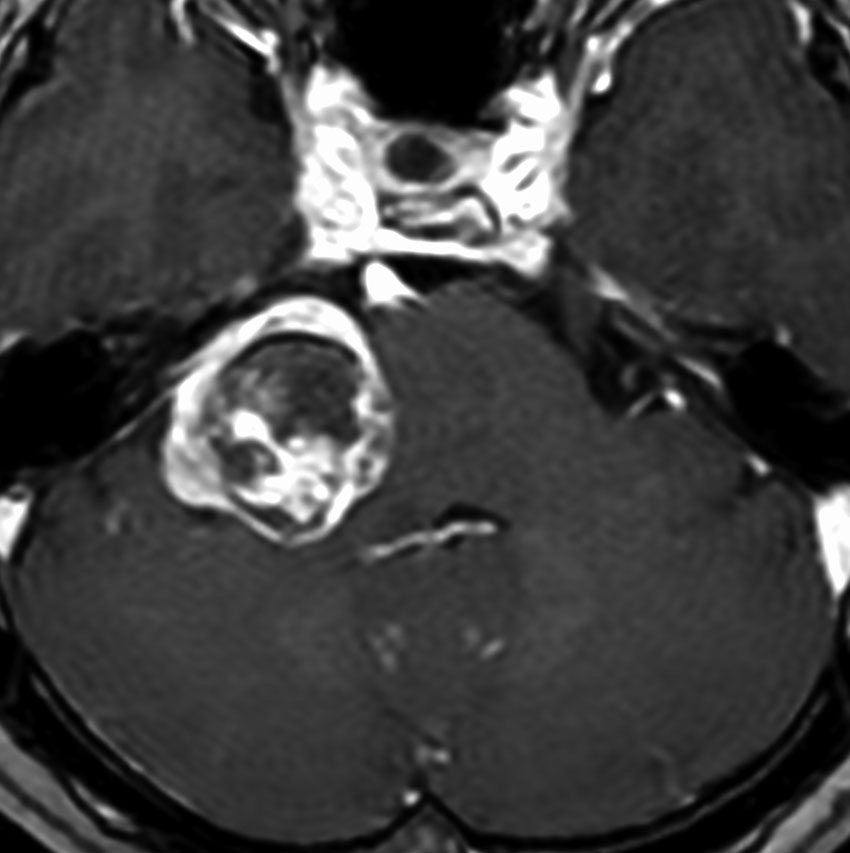

2001年に治療をした,40代女性の大きな聴神経腫瘍です。50グレイ25分割の定位放射線治療を行いました。中央が1年後,右が3年後です。徐々に縮小して手術を必要としませんでした。このサイズの聴神経腫瘍でも放射線治療は選択できるのですが,多くの場合は開頭手術をお勧めするサイズとも言えます。